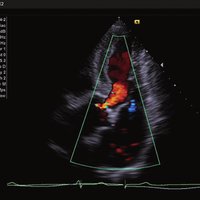

• Color, Power Angio, PW (Pulse Wave) Doppler

Das ACUSON NX2 Ultraschallsystem besitzt eine zukunftsfähige digitale Plattform mit nahezu unerreichter Bildqualität und sorgt für effiziente und zuverlässige Diagnosedaten. Die Vielseitigkeit des Ultraschallsystems wird mit einem großen kompatiblen Portfolio an Schallköpfen gedeckt, und so ist für jeden Anwendungsbereich etwas dabei. Die Bedienkonsole ist intuitiv aufgebaut und optimiert und erlaubt bis zu vier nach vorne gerichteten Schallkopfanschlüssen für eine enorme Effizienz und schnellen Workflow. So lassen sich bei der fetalen Bildgebung außergewöhnlich detailgetreue Darstellungen des Fetus im Gesicht zeigen oder durch die herausragende Farbdopplersensitivität bei der Darstellung der kleinen Gefäße des zystischen Schilddrüsenknotens kleinste Details erkennen. Weiterhin besticht das NX2 mit einfacher Aufrüstbarkeit bei wachsenden Anforderungen für Ihre zukünftigen Anwendungen und kompatible skalierbare Schallköpfe verringern ihren Kapitaleinsatz um bis zu 31 %.

• Kardiologie